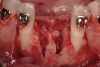

Disadvantages to this technique include time necessary for mesh shaping, manipulation, and fixation. But perhaps the greatest shortcoming of titanium mesh is the necessity of its removal. This requires wide flap reflection and frequently sharp dissection (Figure 1). Often, a dense, soft-tissue layer is found over the mesh, referred to by Boyne10 as a “pseudo-periosteum.” This tenacious soft tissue is tightly bound to the mesh and underlying bone, requiring sharp dissection and elevation of the material. This adds significant operative time to the procedure. This type of soft tissue is shown in Figure 2; the mesh removed at the time of implant placement still has the tissue attached following sharp dissection and elevation. The wide flap reflection and time needed to remove the mesh increases morbidity associated with the second surgical procedure, primarily intended for implant placement. The evolution of this technique has led to the development of a rigid but resorbable mesh. The challenge for clinicians and researchers is to find a resorbable mesh capable of space maintenance comparable to titanium mesh, yet composed of a material that is biocompatible and does not compromise regenerative outcomes.

Figure 2  Tenacious soft tissue incorporates around titanium mesh, which is used for ridge augmentation and removed at time of implant placement.

Figure 2